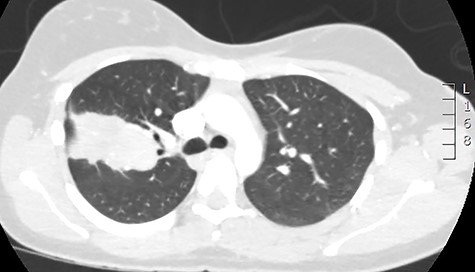

Initial investigations included a full blood panel with inflammatory markers (all within normal range) and a plain chest radiograph which demonstrated a mass in the right upper zone (Fig. 1). Computer tomography pulmonary angiogram (CTPA) scan demonstrated an 8 x 6.5 cm soft-tissue lesion within the right upper lobe (Fig. 2). This mass appeared to extend from the right hilum to the pleural surface and contained multiple small arterial branches. Her delivery date was brought forward pending further investigations. Positron emission tomography CT (PET-CT) demonstrated this lesion to be intensely fluorodeoxyglucose (FDG) avid (Fig. 3).

CT scan demonstrating the large apparent right upper lobe mass.